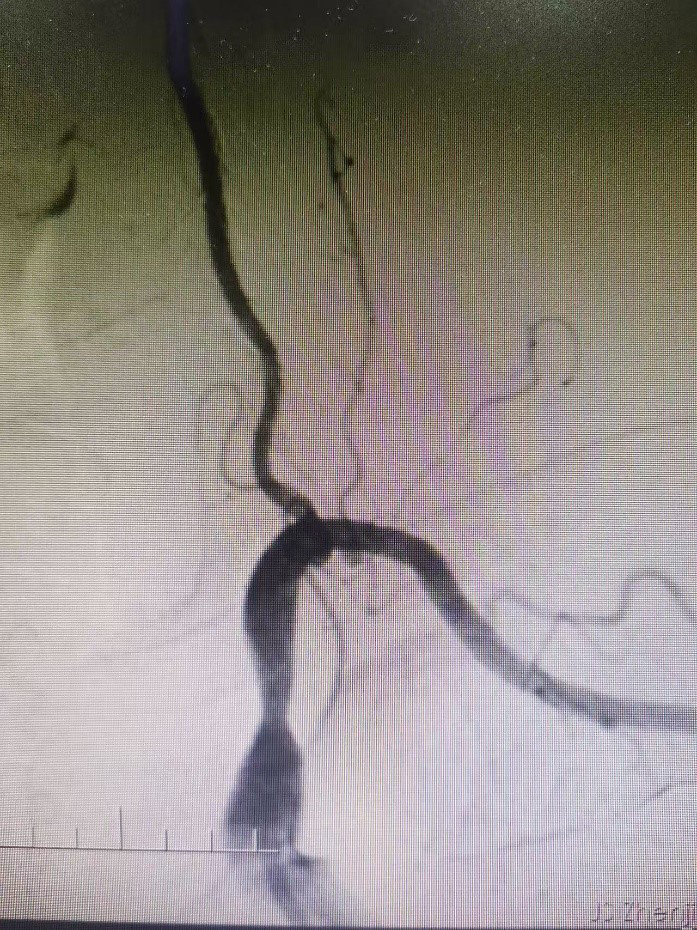

术前

术后

孙银住院进一步检查,DSA血管造影检查显示:左侧锁骨下动脉近端重度狭窄(重度,96%),与陶主任的判断相一致。数字减影血管造影( DSA) 是目前该病诊断的金标准,可以清楚地显示病变位置、程度,有利于明确诊断及指导手术方式的制定。

经陶主任团队综合评估及与患者及家人充分沟通,12月24日局麻下行“锁骨下动脉支架置入术”,并邀请了业内专家现场指导。术中患者神志清晰,顺利置入支架,将闭塞的血管开通,恢复血流。

术后,患者左侧桡动脉搏动有力,左右上肢血压分别是131/74 mmHg、141/85 mmHg,恢复对称,头晕和左上肢乏力症状得到了明显缓解。12月27日,患者已顺利出院。 陶国良表示:由于该患者长期高血压,吸烟病史,血管动脉硬化导致手术操作困难。而“锁骨下动脉支架置入术”有三大难点: